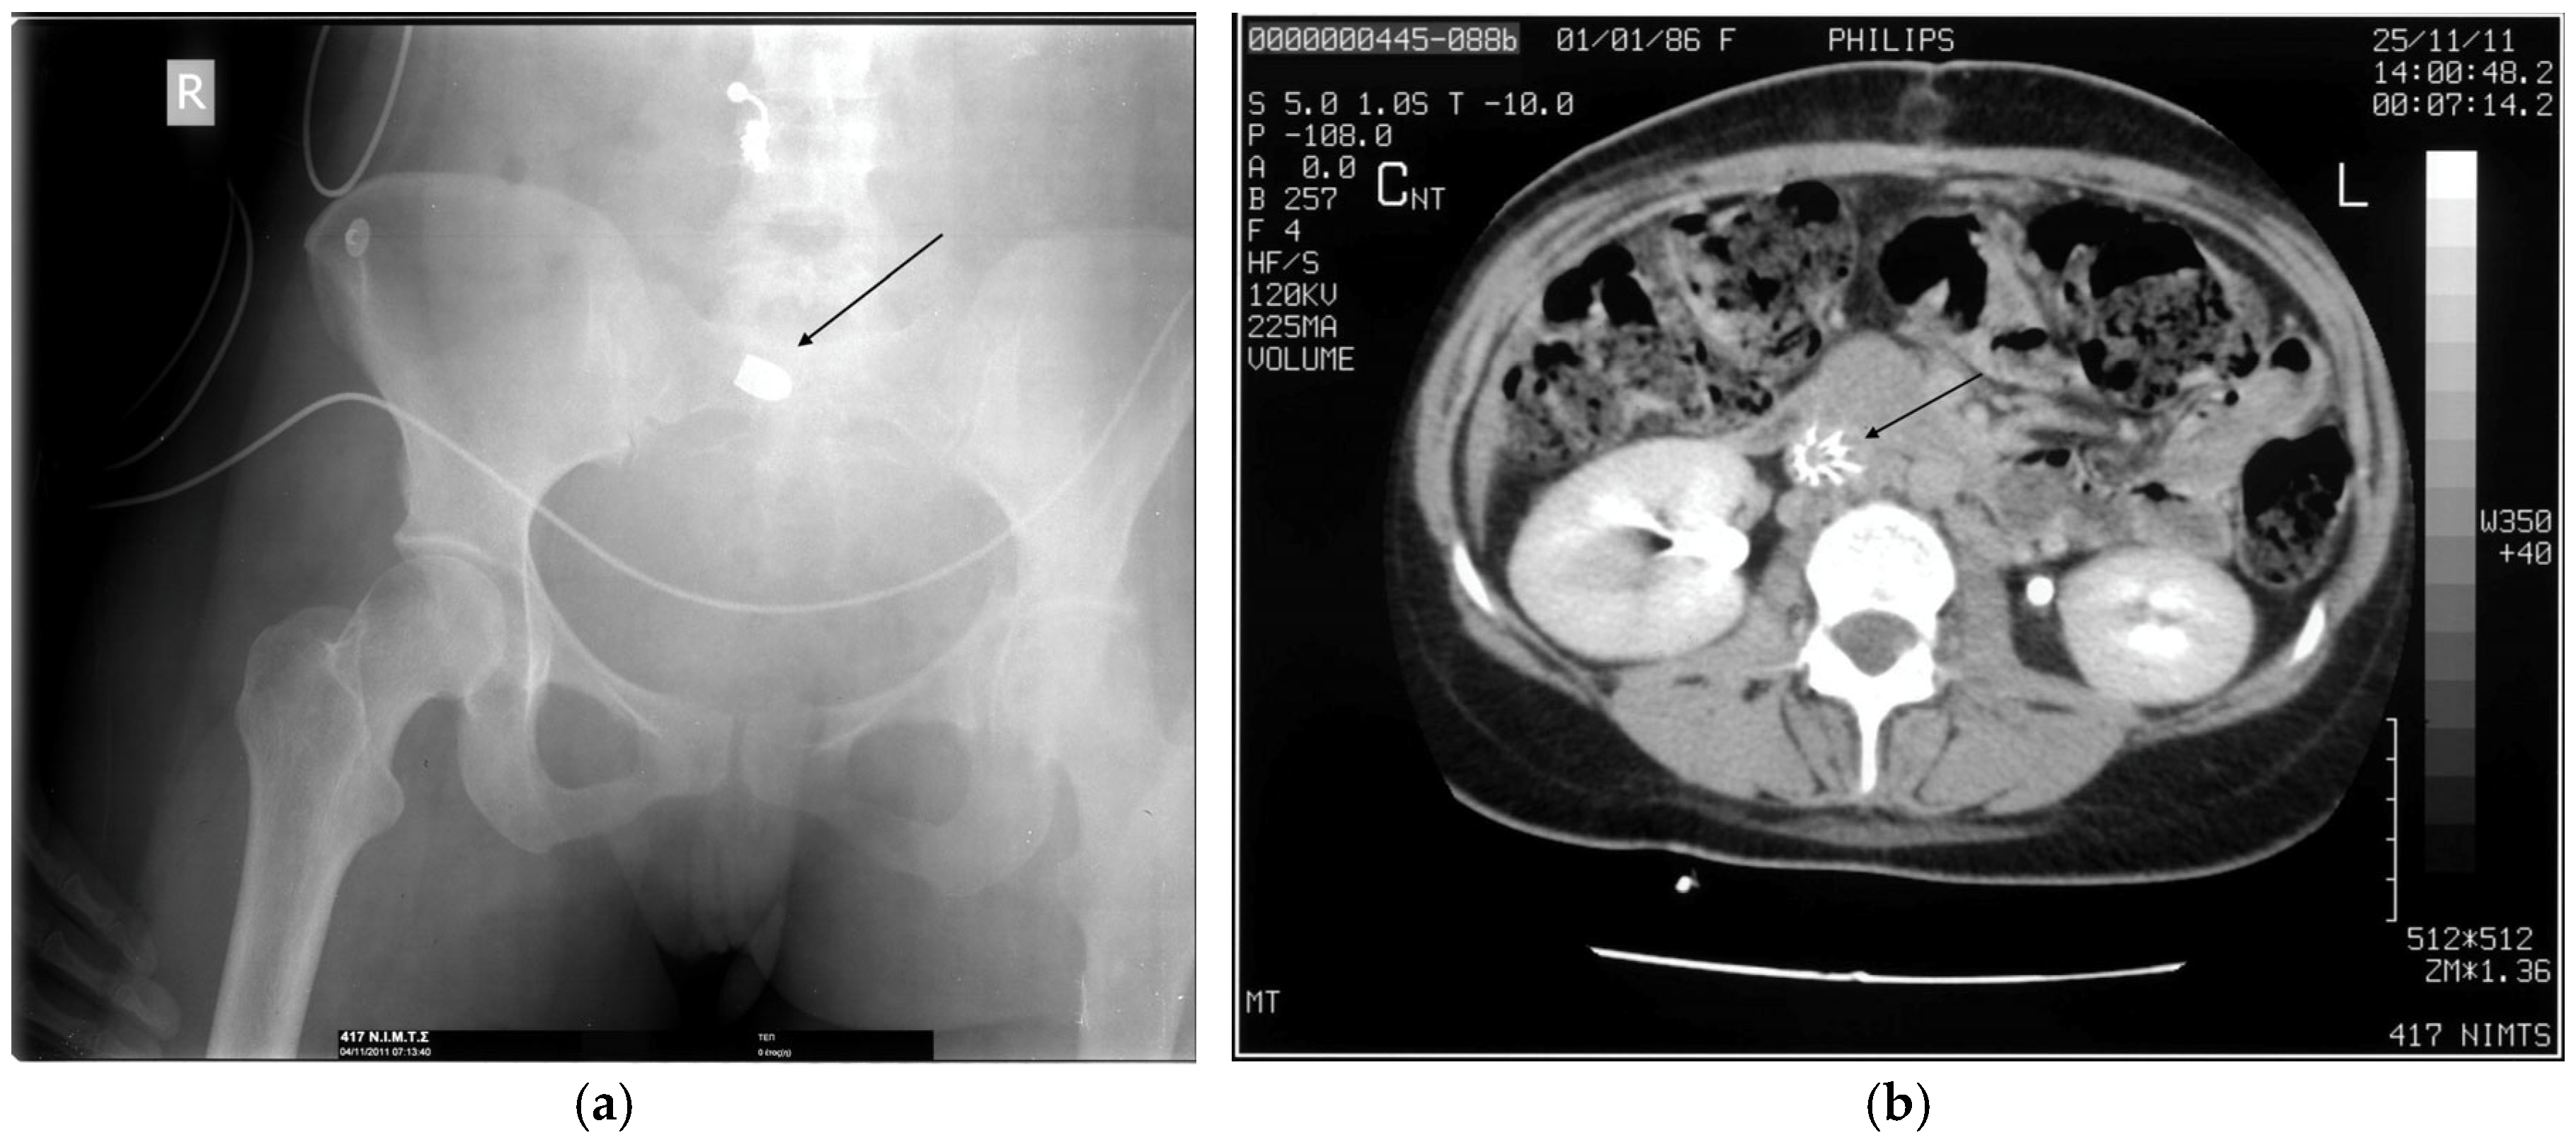

- Reginelli, A.; Russo, A.; Maresca, D.; Martiniello, C.; Cappabianca, S.; Brunese, L. Imaging assessment of gunshot wounds. Semin. Ultrasound CT MR 2015, 36, 57–67. [Google Scholar] [CrossRef]

- Karademir, K.; Gunhan, M.; Can, C. Effects of blast injury on kidneys in abdominal gunshot wounds. Urology 2006, 68, 1160–1163. [Google Scholar] [CrossRef]

- Serafetinides, E.S. Renal and ureteric trauma. In Primer on Urology; Chapple, C.R., Wein, A.J., Eds.; Springer: Cham, Switzerland, 2025; pp. 1013–1024. [Google Scholar] [CrossRef]

- Naeem, M.; Hoegger, M.J.; Petraglia, F.W.; Ballard, D.H.; Zulfigar, M.; Patlas, M.N.; Raptis, C.; Mellnick, V.M. CT of penetrating abdominopelvic trauma. Radiographics 2021, 41, 1064–1081. [Google Scholar] [CrossRef]